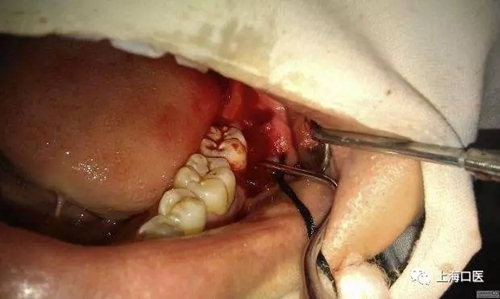

智齒拔除

拔牙干槽癥可怕嗎?

分牙